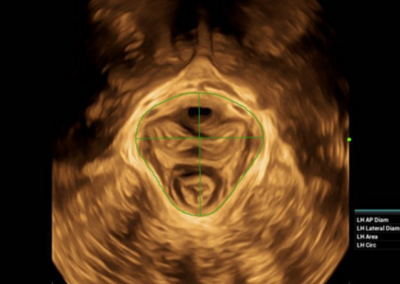

NueWa i9

El Nuewa I9, diseñado exclusivamente para mujeres y atención médica neonatal, brinda una experiencia innovadora integral. Estas innovaciones se desarrollan sobre la base de conocimientos profundos en escenarios clínicos complejos, para proporcionar respuestas precisas y oportunas, una gran eficiencia y una experiencia de usuario extraordinaria. •

- Diseño del panel de control inteligente y específico para exámenes clínicos con teclas especiales de tinta electrónica

- Diseño innovador con diseño adaptable para diferentes situaciones clínicas